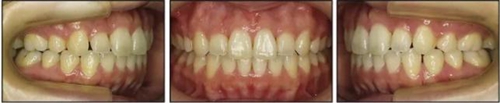

治療后數(shù)據(jù)提示治療目標(biāo)達(dá)成。面相結(jié)果提示微笑及側(cè)貌得到改善(圖6)。達(dá)到了安氏I類尖牙關(guān)系和安氏II類磨牙關(guān)系,形成尖牙保護(hù)合。牙齒中線無偏斜,達(dá)到理想的覆合覆蓋,Spee曲線得到整平。